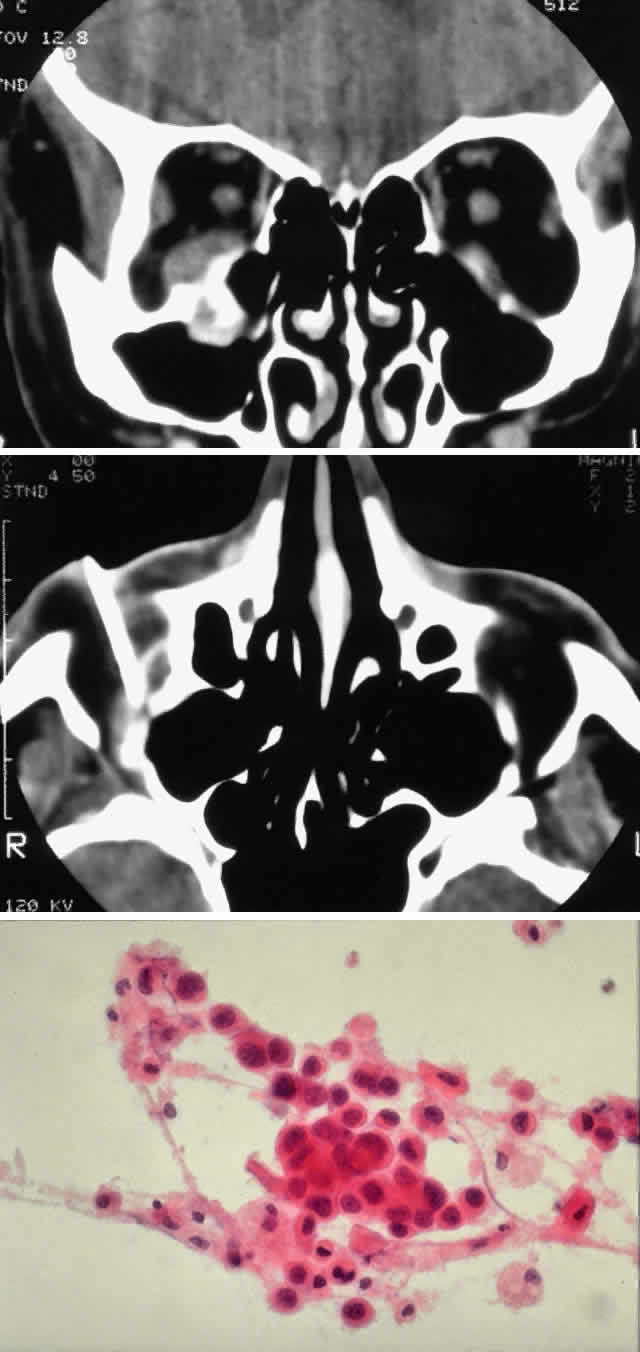

Fig. 2. A 32-year-old woman presented with a 1-month history of sinus congestion and nasal obstruction unresponsive to antibiotics. In the 1 week preceding the initial exam, the right eye became progressively more prominent and showed tearing and redness. On examination, there was mild edema of the lower lid and dysesthesia in the distribution of cranial nerve V2, and the globe was displaced 6 mm laterally and 5 mm anteriorly. There was mild limitation of abduction, chemosis, and nasal choroidal folds. An axial CT scan revealed a diffuse, destructive soft tissue mass centered in the superior nasal passage and ethmoid sinuses extending into the right orbit in contiguity with the medial rectus (A). On enhanced coronal view, the tumor was noted to involve the right maxillary antrum and to extend superiorly into the anterior cranial fossa (B). Biopsy of the sinus (C) revealed an alveolar-type rhabdomyosarcoma (muscle stain, × 320).

Fig. 3. A 73-year-old man presented with a 2-year history of infraorbital numbness and burning sensation, which had progressed to include the supraorbital region, forehead, and lower face during the past 6 months. He had been treated with radiotherapy for prostate carcinoma 7 months before orbital presentation. Examination was significant for proptosis of 2 mm and dysesthesia, including corneal numbness, in all three divisions of cranial nerve V. CT scan revealed a soft tissue mass in the inferior orbit contiguous with the inferior rectus muscle (A). The lesion extended through the infraorbital canal to involve the pterygopalatine fossa and was associated with soft tissue hanging into the upper portion of the maxillary sinus. An axial CT scan-guided aspiration biopsy was performed (B) and revealed squamous cell carcinoma. Groups of cohesive malignant squamous epithelial cells (C) were noted to have pleomorphic nuclei and abundant eosinophilic to orange cytoplasm, with no features of mucinous differentiation (H & E, × 320). (C from White VA, Rootman J: Orbital pathology. In Albert DM, Jakobiec FA (eds): Principles and Practice of Ophthalmology, Vol 4, p 2342. Philadelphia, WB Saunders, 1994.)